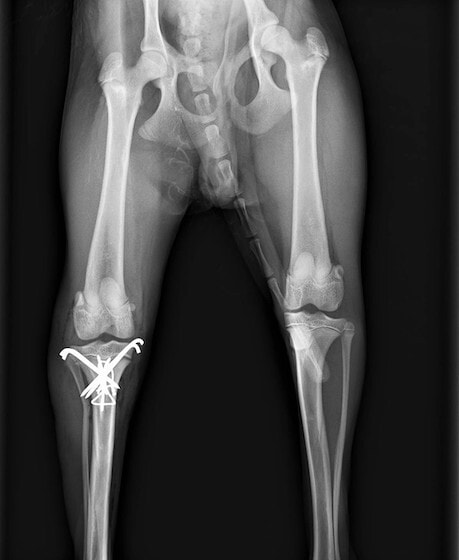

症例3:キルシュナーワイヤーのピンニングによる整復

ペルシャ猫 11ヶ月齢 雄

他院にて左大腿骨遠位の成長板骨折(salter-harrisⅠ型)が認められており、治療相談を目的として来院。当院にて、キルシュナーワイヤーを用いたピンニングにより骨折部位の整復を行いました。術後の経過は良好で、現在も経過観察中です。

術前レントゲン

術後レントゲン